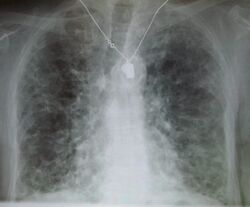

A chest X-ray demonstrating pulmonary fibrosis due to amiodarone

Chest radiography is usually the first test to detect interstitial lung diseases, but the chest radiograph can be normal in up to 10% of patients, especially early in the disease process.[13][14]